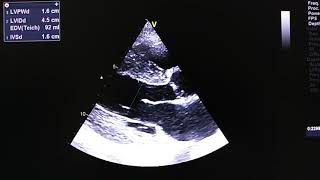

• Hypertensive heart disease (HHD)

Cardiac sonography.